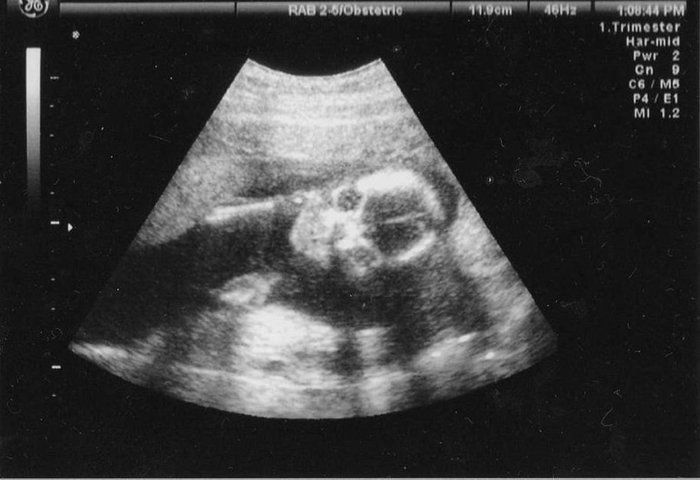

犬飼ねこさんの妊娠18週目のエコー写真

おしりの画像です。この日、女の子と判明。